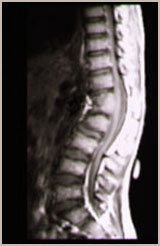

先天性脊柱側凸還有不少患者合併有脊髓異常其中脊髓縱裂,脊髓栓系綜合症是最常見的。因此對於先天性脊柱側凸患者應全面檢查作出正確診斷。 對於先天性脊柱側凸最重要的是判斷側凸的進展,但有時初診時很難作出決定例如某些混合型畸形的患者因為同時存在多種畸形,包括半椎體,骨橋畸形不同的部位可能抵消了相互之間的作用而使脊柱達到平衡,進展可能性小。這樣需要密切隨訪,對畸形進展的潛力作出及時而正確的評估。